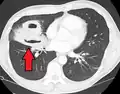

Les abcès pulmonaires sont souvent d'un seul côté et concernent les segments postérieurs des lobes supérieurs et les segments apicaux des lobes inférieurs, car ces zones dépendent de la gravité en position couchée. La présence de niveaux air-fluide implique une rupture dans l'arbre bronchique ou, rarement, la croissance d'un organisme gazogène.[réf. nécessaire]

Abcès pulmonaire à la tomodensitométrie

Un abcès sous-pleural.